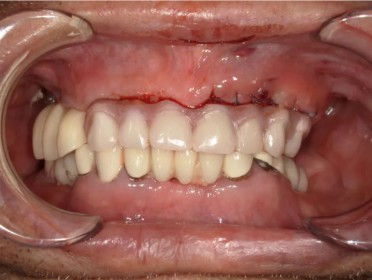

手术当天,凭借术前的充分准备,在两位主任的默契配合下,从拔除患牙到植入种植体,再到安装临时义齿,整个过程仅用两个多小时,创伤小、出血少,丁爷爷全程无明显不适。“手术一点都不痛,医生和护士都特别细心,就像家人一样照顾我。” 术后丁爷爷握着医护人员的手连连道谢并合影留念。

术后,医护团队为丁爷爷制定了细致的护理方案。让家人欣慰的是,丁爷爷术后恢复良好,一周后复查时,他已经逐渐可以尝试软米饭和蔬菜,说话也变得清晰有力。“现在能吃一些软的食物了,现在感觉整个人都精神了!”家人激动地说:“感谢一民医院的医生们,不仅解决了老人的吃饭问题,更让他重拾了生活的乐趣。”